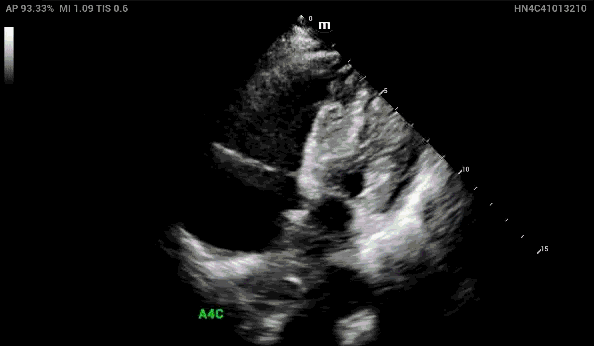

In the apical 4 chamber view, again demonstrated is the dilated right heart concerning for right heart strain.

When looking at the Apical Four Chamber view, how can you confirm that you’re actually looking at the RV and don’t have the probe marker flipped?

1. Tricuspid valve tends to be more near field than the mitral valve

2. Moderator band may be seen in the right ventricle

3. In the apical 5 chamber view, can see the LVOT located in the LV